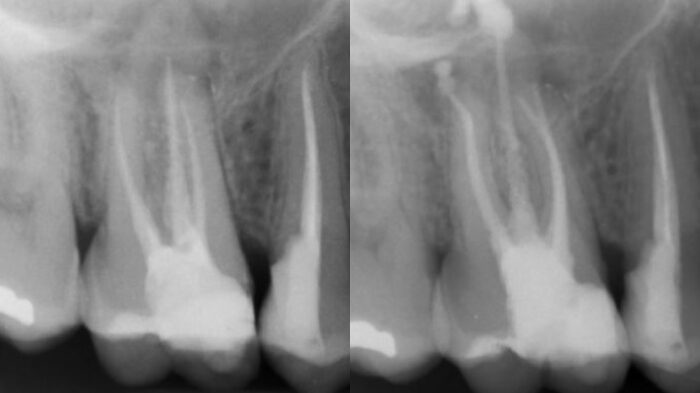

Gaceta Dental hace eco de este nuevo caso clínico donde las limas RetreatAll® de Zarc y las nuevas…